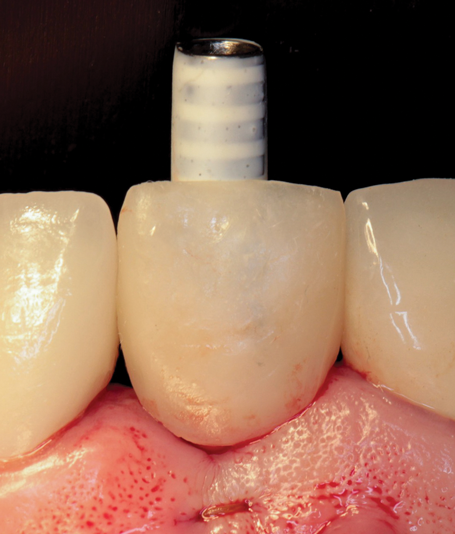

(44.) The provisional restoration was placed back on the implant and tightened to 15 Ncm while applying counter torque. Note that the papillae are partially supported without pressure and that the gingival embrasures are slightly open to allow incisal migration of the papillae during the integration and maturation phase.

Figure 44